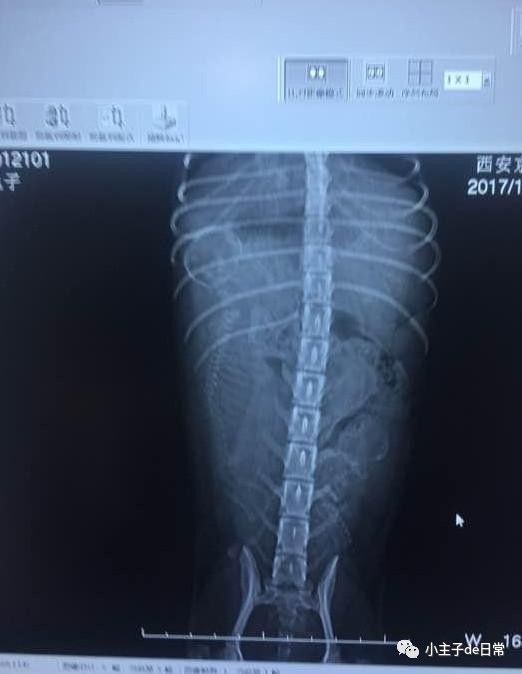

去了医院后,医生照了x光,原来是肚子里的宝宝有的发育很好,又有的发育不良,所以才造成这样的延迟生产,原因就是因为给泰迪妈妈吃的太多的营养。